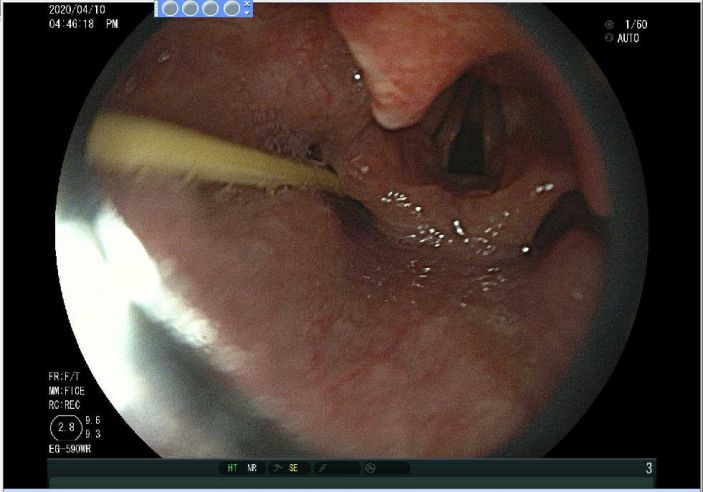

内鏡中心莊義先主任将内窺鏡經患者口腔送至食管入口處,窺鏡下清晰顯示一長約4cm的牙簽,一頭插進咽部左側梨狀窩中,随即用鳄魚取物鉗将牙簽輕輕取出。幸好取出及時,患者并無大礙。

△内窺鏡下清晰可見一長約4cm的牙簽卡在喉嚨中

△牙簽被成功取出。